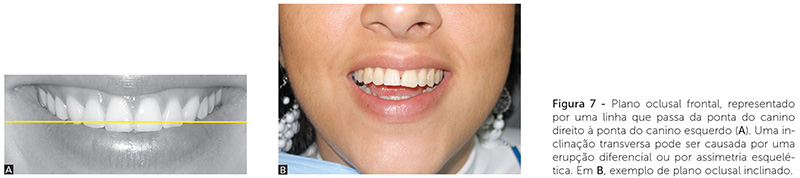

6) Plano oclusal frontal (Fig. 7): representado por uma linha que passa da ponta do canino direito à ponta do canino esquerdo. Uma inclinação transversa pode ser causada por diferença no tempo de erupção ou por assimetria esquelética. O exame clínico é essencial para um diagnóstico diferencial entre a assimetria do sorriso, inclinação do plano oclusal e assimetria facial. A relação da maxila no sorriso não pode ser vista no modelo de estudo.